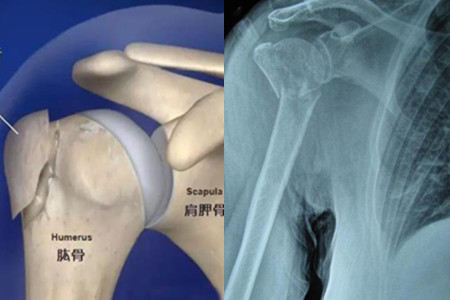

肱骨大节结是手肘上突出的位置,是手臂部位非常重要的组成部位,如果这个地方发生骨折,会给我们的生活带来诸多不方便。发生骨折以后,应该积极配合医生进行治疗,让骨折的地方快速愈合。

当然除了骨折愈合,还应该进行一些运动治疗,不然你的骨头愈合以后就会变得僵硬,再想灵活的活动就非常困难了。下面就来了解右肱骨大节结骨折应该如何进行锻炼恢复,让被这个问题困扰的你能够找到正确的方法。